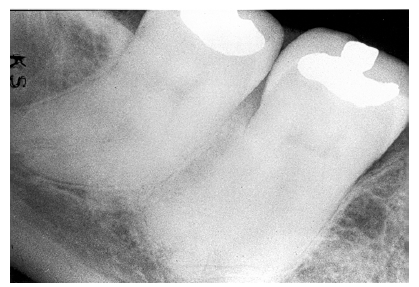

Dentin Caries

Dentin caries extends into the tooth dentin and can be recognized by noting the focal loss of dentinal radiopacity. Most commonly, this darkened dentin is located beneath carious enamel and, typically, the lateral dimension of the dentinal involvement exceeds that of the associated enamel caries (Figure 3). Dentin caries may be discerned interproximally, on the occlusal surface, buccally/lingually, or on root surfaces.

Incipient occlusal dentin caries may be difficult to identify on radiographic images and root caries must be carefully distinguished from cervical burnout, as we will discuss later.

Figure 3 - Dentin Caries

Figure 3